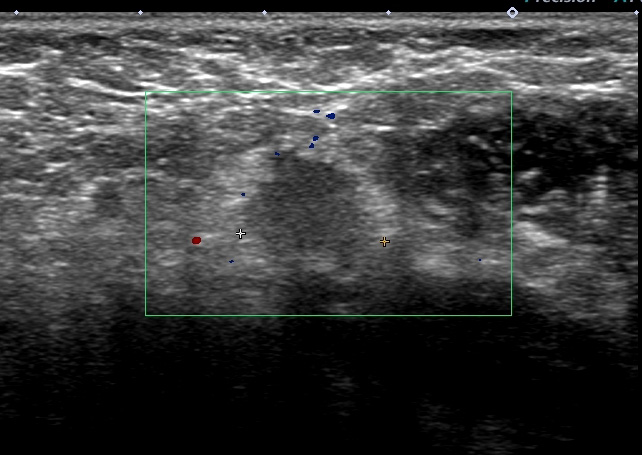

リンパ節の形態を失って「節外浸潤」している

♯そもそも、この大きさ(1.5cm)の細胞診を外していること自体、手技的に「不合格」ですね。

レベル2リンパ節 これが一番大きい 2㎝

形はリンパ節の形をしており「節外」では(画像上)なさそう。